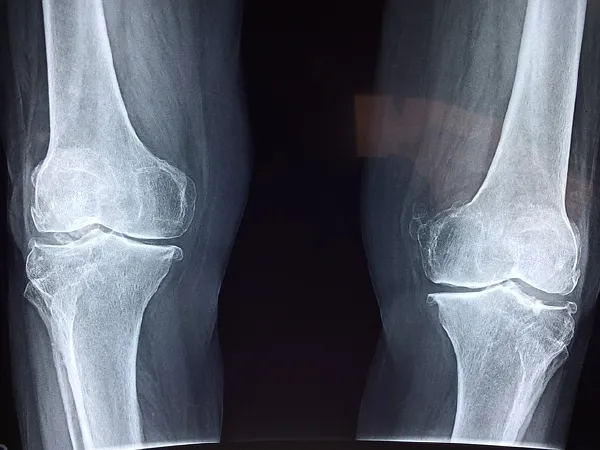

影像学检查是诊断半月板损伤的重要手段。常规的X线片虽然无法直接显示半月板,但能排除其他骨性病变。磁共振成像(MRI)则是目前最常用的检查方法,因为它可以清晰地显示半月板的结构和损伤情况,有助于医生确定损伤的程度和范围,从而制定合理的治疗方案。

影像学分期主要依靠MRI检查,根据半月板损伤的形态特征和严重程度进行分级。Ⅰ级为半月板轻度结构改变,无明显裂痕;Ⅱ级为半月板有局部裂痕,但未贯穿整个半月板;Ⅲ级为半月板裂痕贯穿,甚至有部分结构脱落。这种分期方式更加直观,有助于医生准确判断病情。